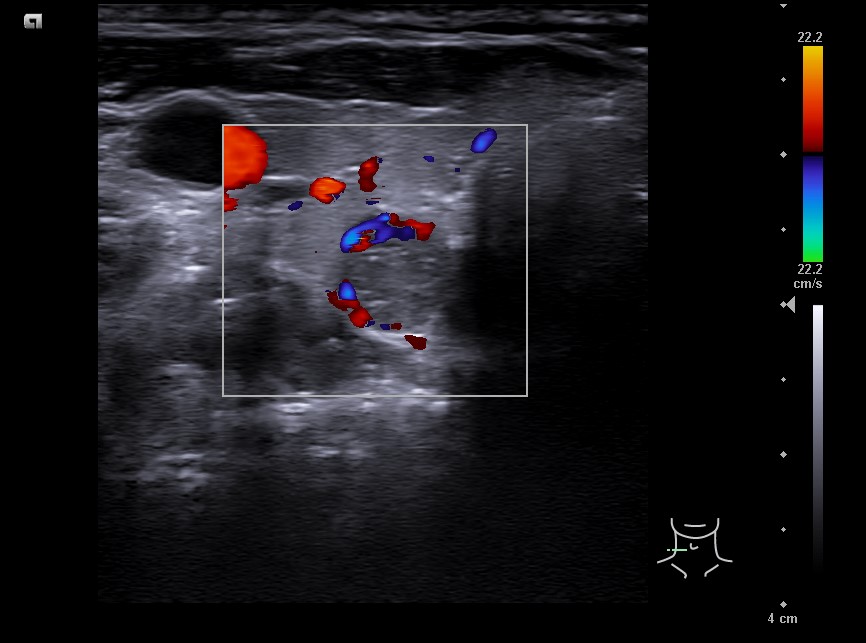

Lóbulo derecho de ecoestrucutra normal. Presenta nódulos hipoecogénicos, pero de características espongiformes y vascularización periférica en situación posteroinferior de 7,5 mm de diámetro, bien definido. TIRADS 2.